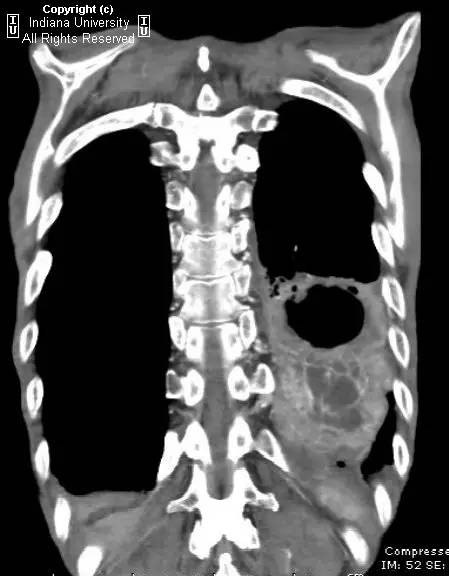

胸片示肺内高度膨胀性病变,膈肌扁平。左后胸部可见较大卵圆形不透亮区并液平面。CT示左肺下叶近后胸壁较大厚壁肿块并部分空洞形成,实性部分不均质强化。右肺下叶可见分叶状结节。左前下少量气胸。

【诊断】鳞状细胞肺癌并后部阻塞性肺炎